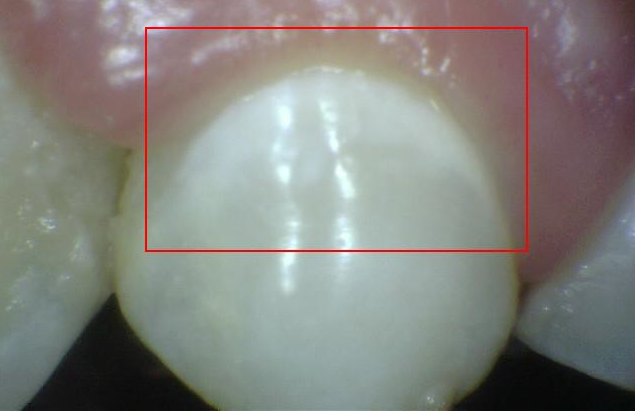

2. CÓDIGO 1

1. Primer cambio visible en esmalte dental, visto seco. Opacidad (blanca) distinguible después del secado con aire o decoloración café confinada a fosa/fisura.

1. DIAGNOSTICO DENTAL: CARIES NO CAVITACIONAL (ACTIVA / NO ACTIVA) Si encontramos esta lesión hacía cervical será activa de lo contrario será no activa

1. TRATAMIENTO: Orientación en normas y educación de higiene oral al padre/madre/menor, control de placa, profilaxis y aplicación de barniz fluorado